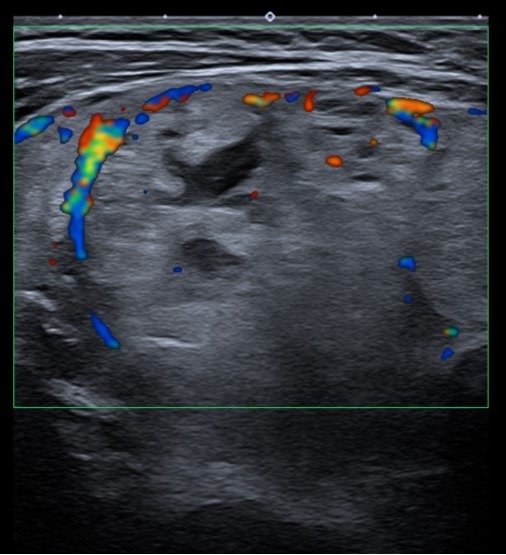

Ausencia de lóbulo izquierdo e istmo, en relación con cambios postquirúrgicos. Lóbulo tiroideo derecho aumentado, ocupado por conjunto de nódulos de aproximadamente 55 × 33 × 70 mm. Múltiples nódulos sólidos de ecogenicidad similar al parénquima; en Doppler se observa vascularización periférica. No se identifican adenopatías.

Se solicita ecografía preferente, cuyas conclusiones coinciden con las observadas: hallazgos compatibles con TI-RADS 3.